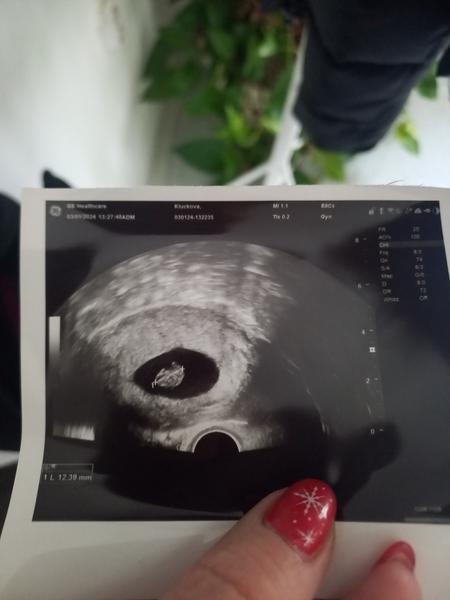

@vanoce2023 Buďte v klidu je to brzo, já byla tak podobně jak vy a byla tam malá tečka a pak včera a už toto

@vanoce2023 teď 8.tyden